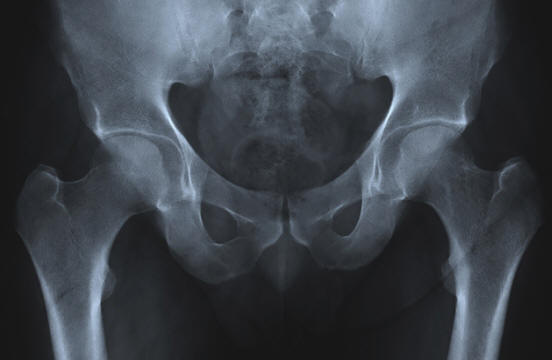

Erittäin tiheät luut

valokuva avoimista lähteistä

Ikääntyminen liittyy väistämättä fyysisen massan esiintymiseen ongelmia. Yleinen esimerkki on osteoporoosi, luukato ja tiheys. Se johtaa väistämättömiin luunmurtumiin lonkat ja ulkonevat humps. Ryhmä ihmisiä kuitenkin omistaa ainutlaatuinen geeni, jossa osteoporoosin hoidon salaisuus on piilotettu.

Tämä geeni löydettiin afrikanerien (eteläafrikkalaiset, joilla on Hollantilainen alkuperä). Se johtaa tosiasiaan, että ihmiset lisätä luumassa koko elämän ajan, ei menettää hänet. Tarkemmin sanottuna tämä on mutaatio SOST-geenissä, joka säätelee proteiinia (sklerostiini), joka säätelee luun kasvua.

Jos afrikkalainen perii kaksi kopiota mutanttigeenistä, hän saa skleroosihäiriö, joka johtaa luiden lisääntymiseen kudos, gigantismi, kasvojen pareesi, kuurous ja varhainen kuolema. On selvää että tämä häiriö on pahempaa kuin osteoporoosi. Mutta jos Afrikaner perii vain yksi kopio geenistä, se saa vain tiheitä luita kokonaisuudelle elämään.

Vaikka tällä hetkellä tämän geenin etuja käytetään vain sen heterotsygoottiset kantajat, tutkijat tutkivat Afrikanersin DNA: ta toivoen löytävänsä tapoja kääntää osteoporoosi ja muut luustohäiriöt. Jo saatujen tietojen perusteella tutkijat ovat aloittaneet sklerostiinin estäjän kliiniset tutkimukset, jotka pystyy stimuloimaan luun muodostumista.